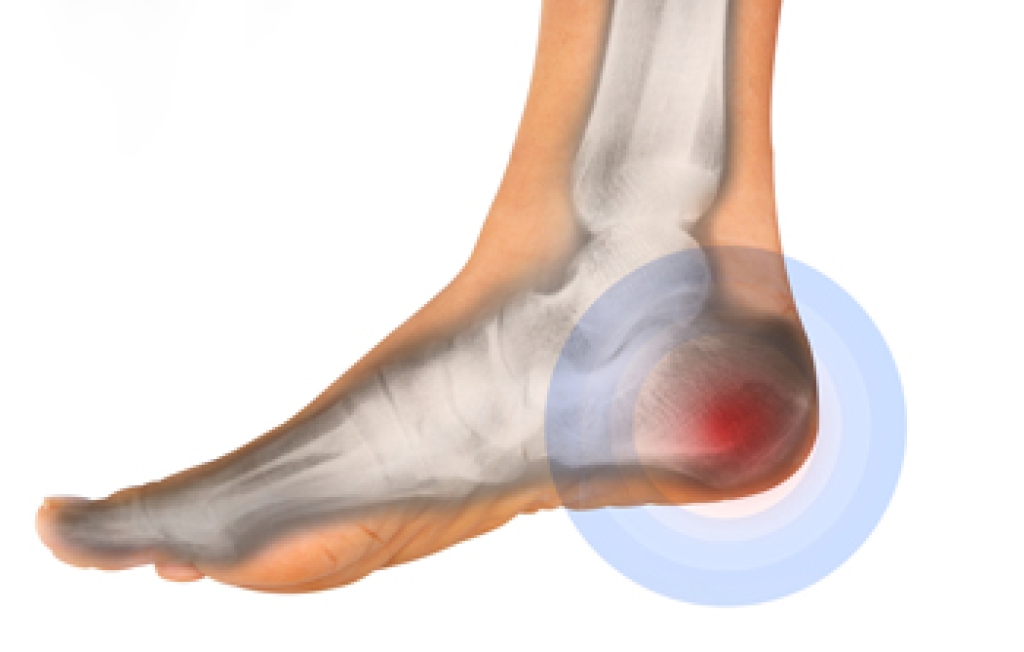

Heel spurs are bony growths that develop on the heel bone due to long-term strain on foot muscles and ligaments. They often form where the plantar fascia connects to the heel, causing discomfort and inflammation. Common causes include repetitive stress, wearing improper footwear, and prolonged standing. Risk factors such as flat feet, obesity, and age can increase the likelihood of developing them. There are two main types. Plantar heel spurs located under the heel and dorsal heel spurs form on the back near the Achilles tendon. Symptoms include sharp pain, tenderness, or stiffness. A podiatrist can diagnose heel spurs through an examination and imaging tests, and provide treatments that reduce pain and improve mobility. If you have heel pain, it is suggested that you schedule a visit with a podiatrist for an accurate diagnosis and treatment.

Heels Spurs

Heel spurs are formed by calcium deposits on the back of the foot where the heel is. This can also be caused by small fragments of bone breaking off one section of the foot, attaching onto the back of the foot. Heel spurs can also be bone growth on the back of the foot and may grow in the direction of the arch of the foot.

Older individuals usually suffer from heel spurs and pain sometimes intensifies with age. One of the main condition's spurs are related to is plantar fasciitis.

Pain

The pain associated with spurs is often because of weight placed on the feet. When someone is walking, their entire weight is concentrated on the feet. Bone spurs then have the tendency to affect other bones and tissues around the foot. As the pain continues, the feet will become tender and sensitive over time.